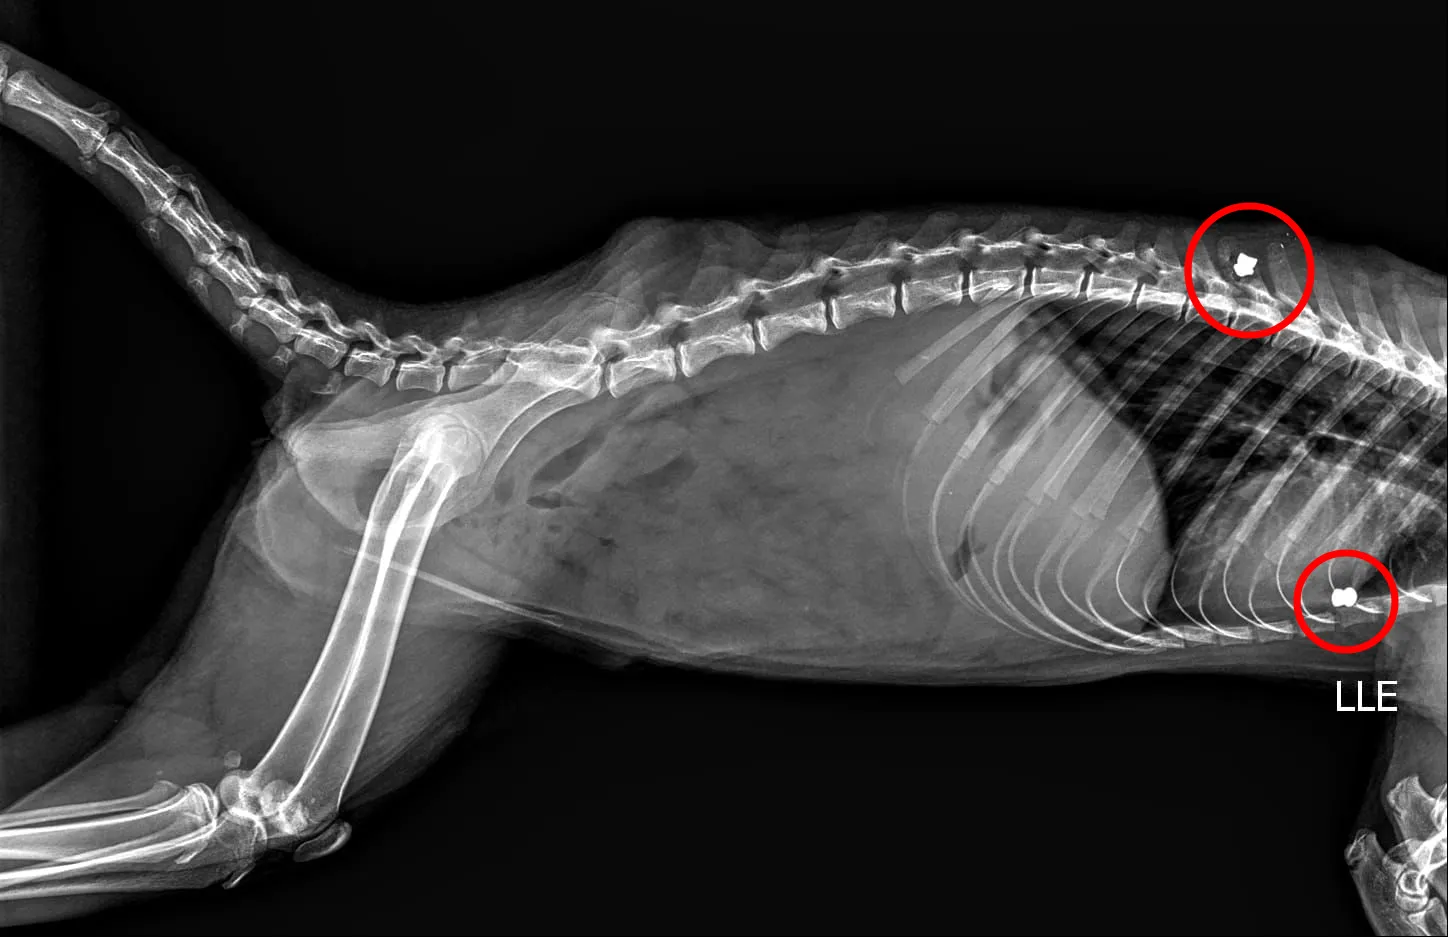

O resgate do animal aconteceu em 15 de abril. A Secretaria do Meio Ambiente agiu rapidamente para levar o quati a um atendimento veterinário especializado. Um exame de raio-X revelou que o animal carregava dois projéteis de chumbinho em seu corpo, um sinal claro da agressão sofrida. Médicos-veterinários trabalham para recuperar a saúde do quati, que segue sob observação.